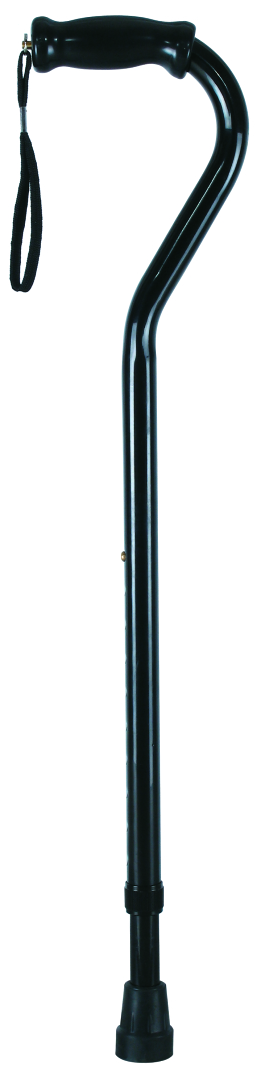

- Crutches

Crutches are an important medical rehabilitation AIDS, branch cane, elbow crutches, axillary crutches, multi-foot crutches, crutches play an important role in walking, not only to provide support and balance, but also to help improve gait and reduce energy consumption